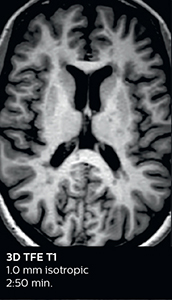

Ingenia Elition 3.0T with Compressed SENSE

3D FLAIR (with Compressed SENSE)

3D FLAIR

1.0 x 1.0 x 1.0 mm*

2:50 min.

3D TSE T1w (with Compressed SENSE)

3D TSE T1w

2:10 min.

3D T2w Drive (with Compressed SENSE)

3D T2w Drive

0.7 x 0.7 x 0.7 mm*

2:52 min.

3D T1w THRIVE (with Compressed SENSE)

3D T1w THRIVE

0.7 x 0.7 x 0.8 mm*

1:30 min.

*true voxel size, without interpolation

Fast MS protocol with optional sequences

The abbreviated MS protocol for brain is only around 9 minutes, so in case of suspected multiple sclerosis, one or two more advanced sequences may be added, such as PSIR (phase sensitive inversion recovery) or susceptibility-weighted sequences to help us make more confident diagnoses in these inflammatory cases.

In this example, the optional 3D multishot susceptibility weighted sequence with 0.6 mm isotropic voxels is 2 lesions with a central vein sign (arrows) and one lesion with a phase-rim sign (arrowhead). The total scan time, including SmartBrain and axial PD/T2 3mm, is 11:10 min. and is 18:30 min. with the optional 3D PSIR and 3D SWI multishot included.